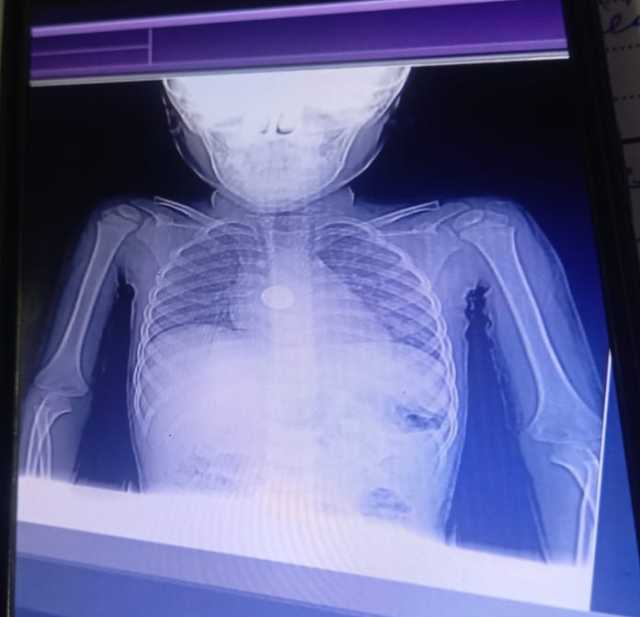

وتابع "عبد الغفار" أنه تم تطوير قسم العلاج الطبيعي بمستشفى أطفال الرمل، في محافظة الإسكندرية بإضافة غرفة لتأهيل أطفال الشلل الدماغي داخل مركز تأهيل الأطفال ذوي الهمم الجديد بالمستشفى، لافتاً إلى تزويد قسم العلاج الطبيعي بمركز الصحة المهنية في الإسكندرية بجهازي أشعة تحت حمراء، ومخدة حرارية ومستلزمات لعلاج أطفال الشلل الدماغي.